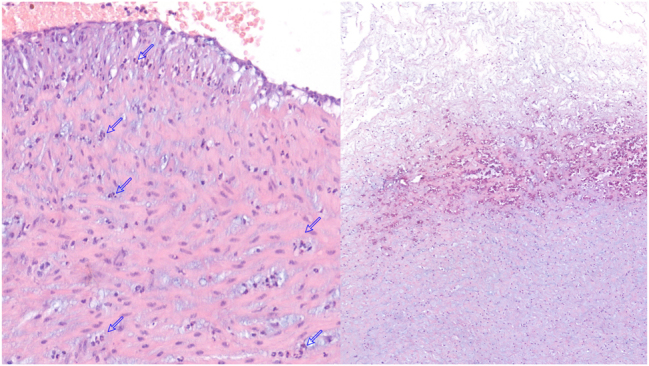

Case presentation: We report a case of intra-amniotic colonisation by C. albicans in a pregnant woman with a previous history of cervical cerclage and candidal vaginosis at 25 weeks of gestational age (GA). The diagnosis was made following preterm premature rupture of membranes at GA 28 weeks and 6 days. Treatment was started with amphotericin B and was replaced by fluconazole due to an anaphylactic reaction. The persistence of C. albicans in the amniotic fluid after 24 days of treatment prompted the decision to plan an elective caesarean delivery at 32 weeks' GA. The infant showed no signs of fungaemia and had an uneventful clinical course after 14 days of treatment with fluconazole.